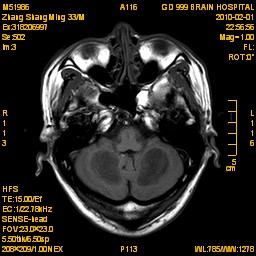

案例1 患者,男,33岁, 海洛因脑病的头颅MR。表现为双侧大脑后部皮层下白质、双侧内囊后肢、枕叶白质、胼胝体压部、中脑、桥脑、双侧小脑半球齿状核质及双侧桥臂多发对称性片状及斑片状长T1长T2异常信号影,FLAIR序列呈高信号,其中双侧内囊后肢表现为特异的“八字征”,双侧小脑半球齿状

核质表现为对称的“蝶翼征”,脑干病变呈“蟹钳征”及“中空征”。增强后双侧半卵圆中心、双侧枕叶白质及双侧小脑半球病变内或边缘中度强化影。给予患者抗炎、脱水、疏通血管及营养神经等药物治疗,一个月后痊愈出院。